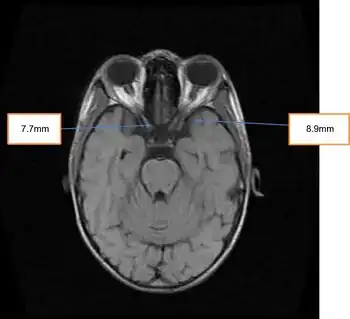

- Increased intracranial pressure manifesting as cerebral edema, papilledema, and headache[3] (may be referred to as Idiopathic intracranial hypertension)